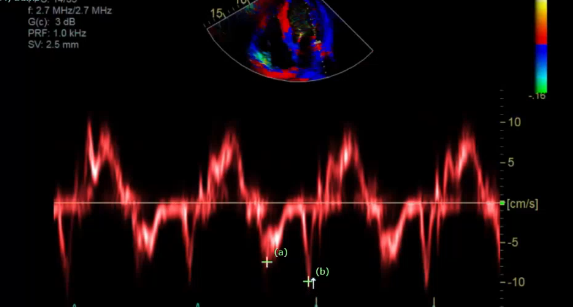

what measurement is this for

Lateral side

Peak lateral e’ and a’